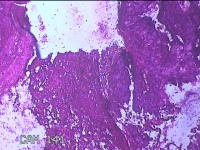

右卵巢黄体囊肿

性别

女

年龄

41岁

临床诊断

右卵巢黄体囊肿破裂

一般病史

下腹痛3小时。

标本名称

大体所见

灰白暗红色囊性肿物2x0.8x0.7cm一个,表面糜烂,切开肿物,内见大量凝血块,囊壁厚约0.1cm。

有点像。不过片子这个效果,没有足够的勇气来诊断。